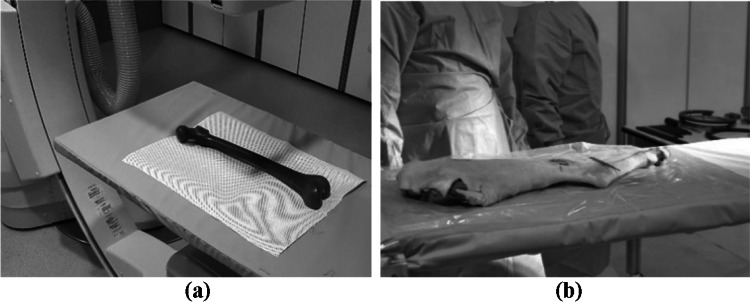

The second experiment involved stitching an actual X-ray image from the C-arm. The human femur phantom and the caprine tibia of a cadaver used for the experiment are shown in Fig. 9. To emulate the clinical configuration, an ex-vivo experiment with the caprine tibia was also conducted. Four X-ray images of the human femur and three X-ray images of the caprine tibia were acquired by the C-arm, as shown in Fig. 10. As in previous experiments, SURF, SIFT, ORB, BRISK, KAZE, the hybrid method, and the proposed method were used, and the resulting images are shown in Fig. 11. Based on the results, all of the methods except for the proposed method failed to stitch the X-ray images. Thus, this experiment confirmed the superiority of the proposed method for X-ray image stitching.

Fig. 9.

Objects imaged with C-arm X-ray imaging. (a) Human femur phantom. (b) Caprine tibia from a cadaver